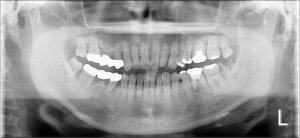

歯周病治療前 歯周病治療後